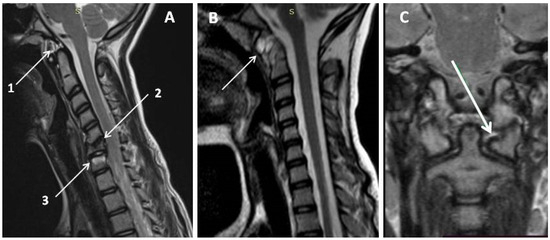

- Ankylosis of the articular joints. Usually, these changes are observed in C2–C3. Ankylosis can result in impaired vertebral body growth, especially in patients with early-onset JIA [3].

- Atlantoaxial instability. Anterior subluxation of the atlas is characterized by an increase in the distance between the anterior C1 semicircle and the dens of C2. The anterior atlantodental interval (AADI) is the horizontal distance between the posterior cortex of the anterior arch of the atlas (C1) and the anterior cortex of the dens in the median (midsagittal) plane.

- 3.

- Atlantoaxial rotational locking. Damage to the joint capsule or ligament apparatus of the atlantoaxial joint can lead to the development of rotational subluxation of C1. With prolonged dislocation, the capsule and ligaments become tightened, which leads to chronic atlantoaxial block. A typical clinical manifestation of a rotational subluxation is a malposition of the head with a slight (about 20°) tilt to one side and rotation to the opposite side. Risk factors for the possible transition of subluxation into chronic block include the contraction of the joint capsule, intra-articular fibrous inclusions, synovitis of the adjacent joint surfaces, formation of C1 and C2 vertebrae bony fusions, and secondary deformity of the surface of the facet joints [20].